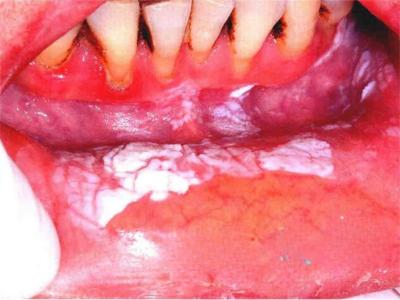

唇内侧

白斑

口腔毛状黏膜白斑唇内侧黏膜白斑图

口腔毛状黏膜白斑多见于艾滋病患者,病损累及唇内侧,呈白色或乳白色,一大片,稍突起于黏膜,表面粗糙,呈毛状,应及时遵医嘱进行治疗。